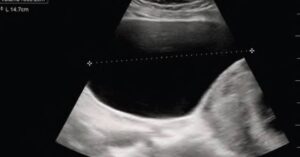

urinary retention women jan 2024 figure 1 featured

• Case Report: Acute Urinary Retention in a Pregnant Woman